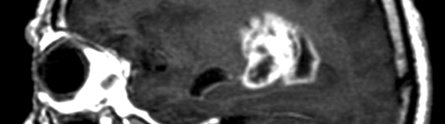

A brain scan

The brain was then scanned using CT and MRI technology to demonstrate that it is still possible to distinguish the polymer from normal brain tissue on a routine brain scan, an aspect crucial for doctors when dealing with follow-up care for brain tumour patients who have undergone surgery.